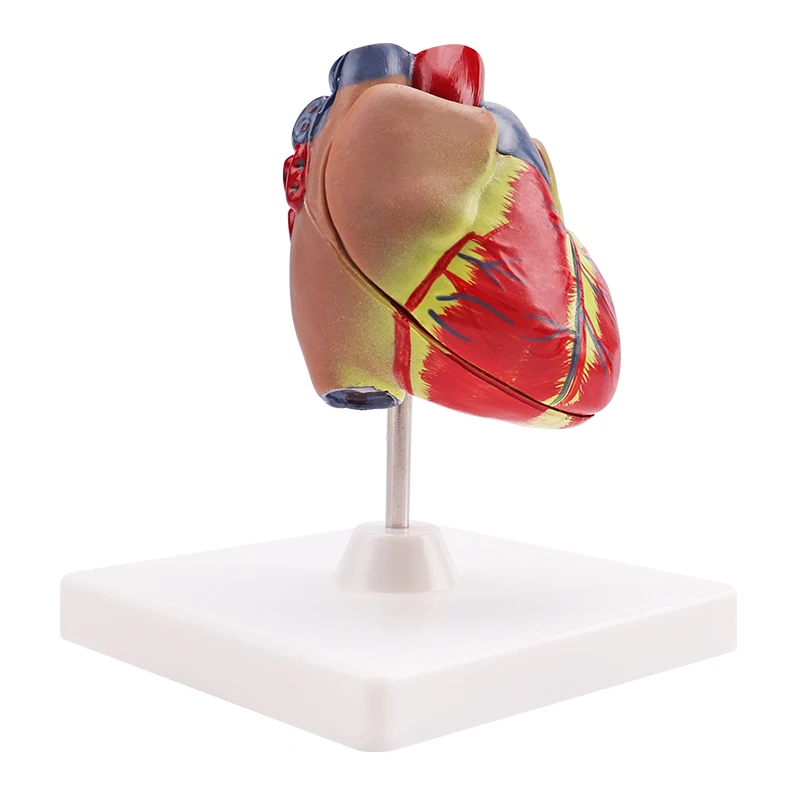

Valentine’s Day ช็อกโกแลตหัวใจ 12 ชิ้น – ของขวัญรังนกแท้ คอซซี่ โมเดลหัวใจมนุษย์ (Human Heart) | Shopee Thailand

โมเดลหัวใจมนุษย์ (Human Heart) | Shopee Thailand หัวใจมนุษย์ ภาพสต็อก – ดาวน์โหลดรูปภาพตอนนี้ – หัวใจ – อวัยวะภายใน …

ขยายกายวิภาคหัวใจมนุษย์รุ่น 3 ชิ้นส่วน – Buy กายวิภาคหัวใจ,หัวใจ … หัวใจมนุษย์ การออกแบบรายละเอียด ภาพประกอบสต็อก – ดาวน์โหลดรูปภาพตอนนี้ …

ForgetMeNot: Dessert strawberries with chocolate and cream | ช็อกโกแลต … ชีวิตพลาสติกกายวิภาคหัวใจมนุษย์รุ่น2ชิ้นส่วน – Buy การสอนรุ่น,Anatomy …

ชีวิตพลาสติกกายวิภาคหัวใจมนุษย์รุ่น2ชิ้นส่วน – Buy การสอนรุ่น,Anatomy … ช็อคโกแลตรูปหัวใจ [ภาพวาดฟรี] | OkusanPix

หัวใจวิทยาศาสตร์เรื่องกายวิภาคศาสตร์ทางการแพทย์หัวใจมนุษย์รุ่นขาย – Buy … รูปเวกเตอร์ฟรีหัวใจการ์ตูนปุ่ม PNG , หัวใจมนุษย์, หัวใจ, เซลล์ภาพ PNG …

ชีวิตพลาสติกกายวิภาคหัวใจมนุษย์รุ่น2ชิ้นส่วน – Buy การสอนรุ่น,Anatomy … ขนมช็อกโกแลตแท่ง ตรา โชกี้ โชกี้ 1 บาท แพ็ค 100 ชิ้น | Shopee Thailand

ขนมช็อกโกแลตแท่ง ตรา โชกี้ โชกี้ 1 บาท แพ็ค 100 ชิ้น | Shopee Thailand ชีวิตพลาสติกกายวิภาคหัวใจมนุษย์รุ่น2ชิ้นส่วน – Buy การสอนรุ่น,Anatomy …

ชีวิตพลาสติกกายวิภาคหัวใจมนุษย์รุ่น2ชิ้นส่วน – Buy การสอนรุ่น,Anatomy … รักสุดใจ! ช่อช็อกโกแลตให้เธอ รวมไอเดียช่อช็อกโกแลตสื่อรัก มอบให้แฟน

รักสุดใจ! ช่อช็อกโกแลตให้เธอ รวมไอเดียช่อช็อกโกแลตสื่อรัก มอบให้แฟน แบบจำลองหัวใจมนุษย์ขนาดชีวิตที่มีสีพื้นโปร่งใสโรคหัวใจทางการแพทย์แบบ …

แบบจำลองหัวใจมนุษย์ขนาดชีวิตที่มีสีพื้นโปร่งใสโรคหัวใจทางการแพทย์แบบ … Chocolate Heart, Hand-drawn sketch Chocolate s, brown, food png | PNGEgg

Chocolate Heart, Hand-drawn sketch Chocolate s, brown, food png | PNGEgg แบบจำลองหัวใจมนุษย์ขนาดชีวิตที่มีสีพื้นโปร่งใสโรคหัวใจทางการแพทย์แบบ …

แบบจำลองหัวใจมนุษย์ขนาดชีวิตที่มีสีพื้นโปร่งใสโรคหัวใจทางการแพทย์แบบ … ช็อกโกแลต รูปฟุตบอล เหรียญทอง หัวใจ บรรจุ 60 ชิ้น | Shopee Thailand

In-306 3d กายวิภาคศาสตร์หัวใจมนุษย์รูปแบบทางการแพทย์พลาสติกกายวิภาค … หัวใจมนุษย์ ภาพสต็อก – ดาวน์โหลดรูปภาพตอนนี้ – หัวใจ – อวัยวะภายใน, การ …

หัวใจวิทยาศาสตร์เรื่องกายวิภาคศาสตร์ทางการแพทย์หัวใจมนุษย์รุ่นขาย – Buy … หัวใจวิทยาศาสตร์เรื่องกายวิภาคศาสตร์ทางการแพทย์หัวใจมนุษย์รุ่นขาย – Buy …

หัวใจวิทยาศาสตร์เรื่องกายวิภาคศาสตร์ทางการแพทย์หัวใจมนุษย์รุ่นขาย – Buy … Anatomy หัวใจมนุษย์รุ่นพลาสติกทางการแพทย์กายวิภาคหัวใจจัมโบ้รุ่นอวัยวะ …

Anatomy หัวใจมนุษย์รุ่นพลาสติกทางการแพทย์กายวิภาคหัวใจจัมโบ้รุ่นอวัยวะ … รูปช็อกโกแลตหัวใจพร้อมน้ำเชื่อม PNG , วาเลนไทน์วัน, หัวใจ, วันแห่งความ …

3d Anatomy หัวใจมนุษย์รุ่นพลาสติกทางการแพทย์กายวิภาคหัวใจจัมโบ้รุ่น … หัวใจวิทยาศาสตร์เรื่องกายวิภาคศาสตร์ทางการแพทย์หัวใจมนุษย์รุ่นขาย – Buy …

หัวใจวิทยาศาสตร์เรื่องกายวิภาคศาสตร์ทางการแพทย์หัวใจมนุษย์รุ่นขาย – Buy … ส่งไว🚀24ชม. เจบีช็อกโกแลต รูปฟุตบอล เหรียญทอง เหรียญเงิน ทองแท่ง หัวใจ …

ส่งไว🚀24ชม. เจบีช็อกโกแลต รูปฟุตบอล เหรียญทอง เหรียญเงิน ทองแท่ง หัวใจ … Anatomy หัวใจมนุษย์รุ่นพลาสติกทางการแพทย์กายวิภาคหัวใจจัมโบ้รุ่นอวัยวะ …

Anatomy หัวใจมนุษย์รุ่นพลาสติกทางการแพทย์กายวิภาคหัวใจจัมโบ้รุ่นอวัยวะ … ภาพประกอบแบนเวกเตอร์หัวใจมนุษย์ขนาดใหญ่บนพื้นหลังสีขาว ภาพประกอบสต็อก …

หัวใจมนุษย์กายวิภาครุ่นวิทยาศาสตร์การแพทย์รูปแบบการสอน ห้องหัวใจมนุษย์: คำอธิบายโครงสร้างหน้าที่และประเภท

หุ่นจำลองหัวใจมนุษย์ 3d มนุษย์กายวิภาครุ่นหัวใจมนุษย์สำหรับซัพพลายเออร์แบบครบวงจรวิทยาศาสตร์ …

3d มนุษย์กายวิภาครุ่นหัวใจมนุษย์สำหรับซัพพลายเออร์แบบครบวงจรวิทยาศาสตร์ … 3d Anatomy หัวใจมนุษย์รุ่นพลาสติกทางการแพทย์กายวิภาคหัวใจจัมโบ้รุ่น …

3d Anatomy หัวใจมนุษย์รุ่นพลาสติกทางการแพทย์กายวิภาคหัวใจจัมโบ้รุ่น … อวัยวะหัวใจของมนุษย์ | องค์ประกอบกราฟฟิก แบบ PSD ดาวน์โหลดฟรี – Pikbest

หัวใจมนุษย์กายวิภาครุ่นวิทยาศาสตร์การแพทย์รูปแบบการสอน 15 Porch ช็อกโกแลต Fudge แม่พิมพ์ซิลิโคนหัวใจรูปเค้กช็อกโกแลตตกแต่ง DIY …

121,300+ หัวใจมนุษย์ ภาพถ่าย ภาพถ่ายสต็อก รูปภาพ และภาพปลอดค่าลิขสิทธิ์ … อุปกรณ์การศึกษากายวิภาคศาสตร์รุ่นหัวใจมนุษย์รุ่นสำหรับโรงเรียนขนาดชีวิต …

อุปกรณ์การศึกษากายวิภาคศาสตร์รุ่นหัวใจมนุษย์รุ่นสำหรับโรงเรียนขนาดชีวิต … วิธีทำ “นามะช็อกโกแลต” ของฝากยอดฮิตจากญี่ปุ่น อร่อยหรูดูแพง แต่ทำง่าย …

In-306 3d กายวิภาคศาสตร์หัวใจมนุษย์รูปแบบทางการแพทย์พลาสติกกายวิภาค … บอลลูนหัวใจมนุษย์ Angioplasty เวกเตอร์ ภาพประกอบ ภาพประกอบสต็อก – ดาวน์ …

The Heart หัวใจมนุษย์ 心脏 โรงงานโดยตรงขาย Anatomy หัวใจมนุษย์การฝึกอบรมชุดอวัยวะภายในรุ่น – Buy …

โรงงานโดยตรงขาย Anatomy หัวใจมนุษย์การฝึกอบรมชุดอวัยวะภายในรุ่น – Buy …